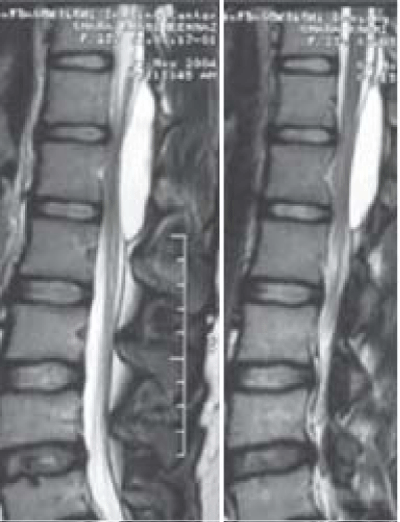

10 patients had total cyst excision after laminectomy (Figure 3). A solitary dural defect was found in 10 patients and could be tightly closed. Multiple dural defects were found in one case and couldn’t be closed. A shunt between the cystic cavity and subarachnoid space was performed for this patient.

Figure 3: Cyst excision after laminectomy.